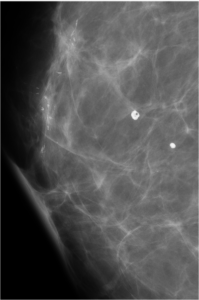

48 year old female came for routine mammographic screening...

Read More